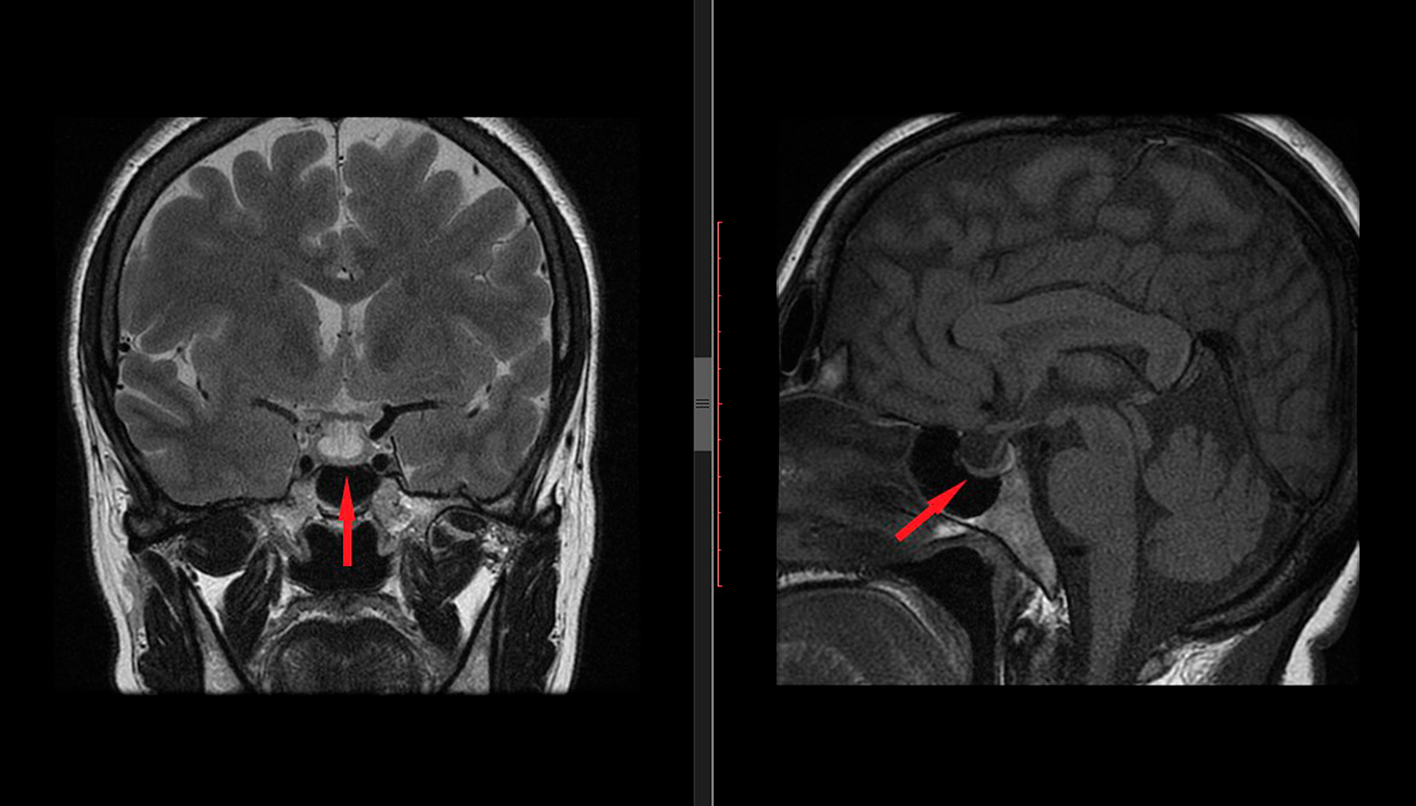

Apoplejía hipofisiaria

La apoplejía hipofisiaria es una afección grave que afecta la glándula pituitaria en el cerebro. Esta glándula se encuentra en la base del cerebro, y es una de las glándulas endocrinas más importantes del cuerpo. Dicha glándula produce hormonas que ayudan a regular el crecimiento, el metabolismo y la reproducción.

Esta condición se produce cuando un tumor en la glándula pituitaria crece y comienza a presionar el tejido circundante. Esto puede causar que el flujo sanguíneo al área se vea interrumpido, lo que resulta en una hemorragia en esa área. Esta hemorragia a su vez, daña la glándula pituitaria y causa una serie de síntomas que incluyen:

Los síntomas y su severidad pueden variar en cada paciente dependiendo de la posición de la hemorragia. Debido a la naturaleza grave de este trastorno, la apoplejía hipofisiaria requiere tratamiento inmediato.